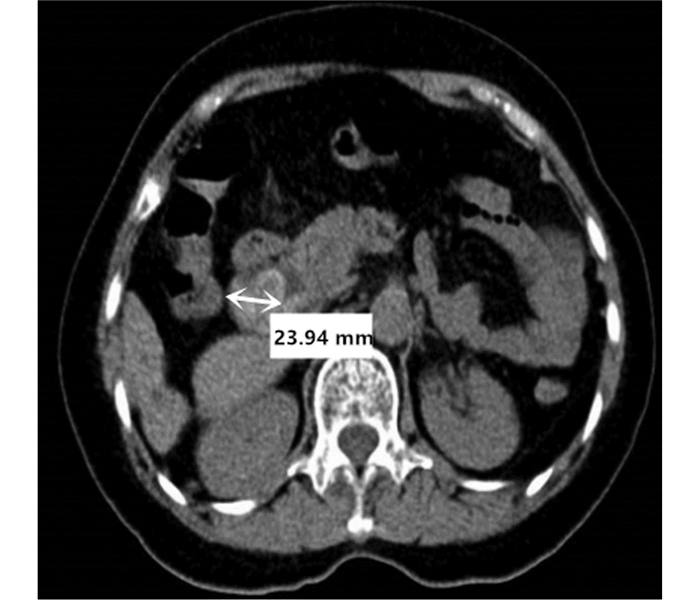

Primary fibrosarcoma of the liver misdiagnosed as hepatic abscess: A case report

Liuyang ZHU, Jiancun HOU, Long YANG, Wen TONG, Yamin ZHANG

2021, 37(7): 1665-1667. DOI: 10.3969/j.issn.1001-5256.2021.07.037

Abstract(896) HTML (266) PDF (3350KB)(81)

Abstract: